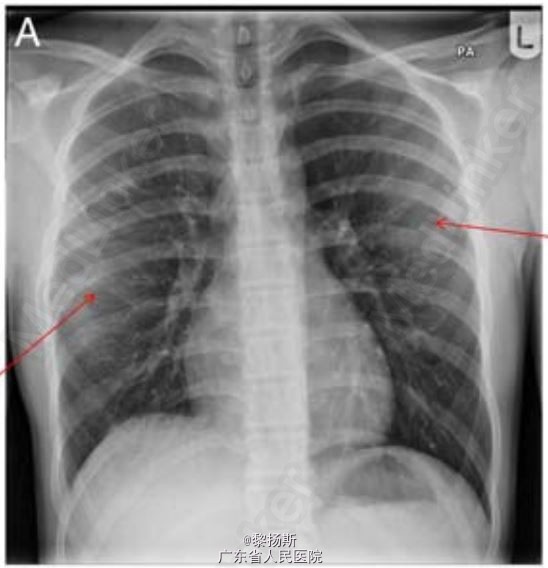

14 岁男孩,因右侧胸痛、咳嗽伴间歇性发热 2 周到我院儿科急诊就诊。胸片所见如(图 1A),就诊后嘱托患者若症状无缓解则需再次返院就诊。1 周后患者再次就诊,呼吸费力、胸痛、体温最高达 38.5℃。

体查检查发现右侧胸部叩诊浊音,呼吸音减弱。复查胸片结果见图 1B。 首次就诊血液学检查白细胞计数正常,C 反应蛋白升高(303 mg/L)。患儿呼吸急促,需要吸氧 1-2L/min,同时对患者静脉用克拉维酸和克拉霉素。胸部超声证实存在大量胸腔积液,疑诊脓胸,遂转入我科进一步治疗。

诊断:骨性类外生骨疣相关性血胸;在超声介导下行右半胸腔穿刺引流,引流出 750 ml 深黑色的血性液体,而非脓液。除了收集右侧胸部的胸腔积液外,患者右侧第 4 肋前部末端可见一肋外生骨疣。同时第 5 肋连接处可见一结构畸形。另一个外生骨疣可见于左侧第 7 肋后部末端(图 2B)。患者曾多次手术切除位于膝部、肩部和前臂的良性骨性外生骨疣。右侧桡骨可触及一个质地不柔软的 3×2 cm 的骨性肿块。患者一直在整形外科随访,无骨痛或关节疼痛,本次发病前患儿无任何不适。无骨科疾病家族史。该患者接受抗生素治疗疗效较好,同时采用可视胸腔镜为患儿吸除血块和行胸腔冲洗。胸腔积液培养阴性。随后患者康复出院。

该病例旨在提醒医者们即使已经在胸片上发现明显的异常改变,仍应仔细查看胸片,在患儿初次就诊时就医者就忽略了外生骨疣这一改变。先天性多发性外生骨疣(HME)以及实性肋外生骨疣为肋外生骨疣的两种不同类型。HME 为常染色体显性遗传病,外生骨疣常见于四肢的长骨(图 3)。HME 患者的生长可能会受到限制,使得四肢长度不成比例,身材矮小。实性类外生骨疣患者则表现相反,外生骨疣常不对称性生长,无家族史。引自Thorax doi:10.1136/thoraxjnl-2015-207061